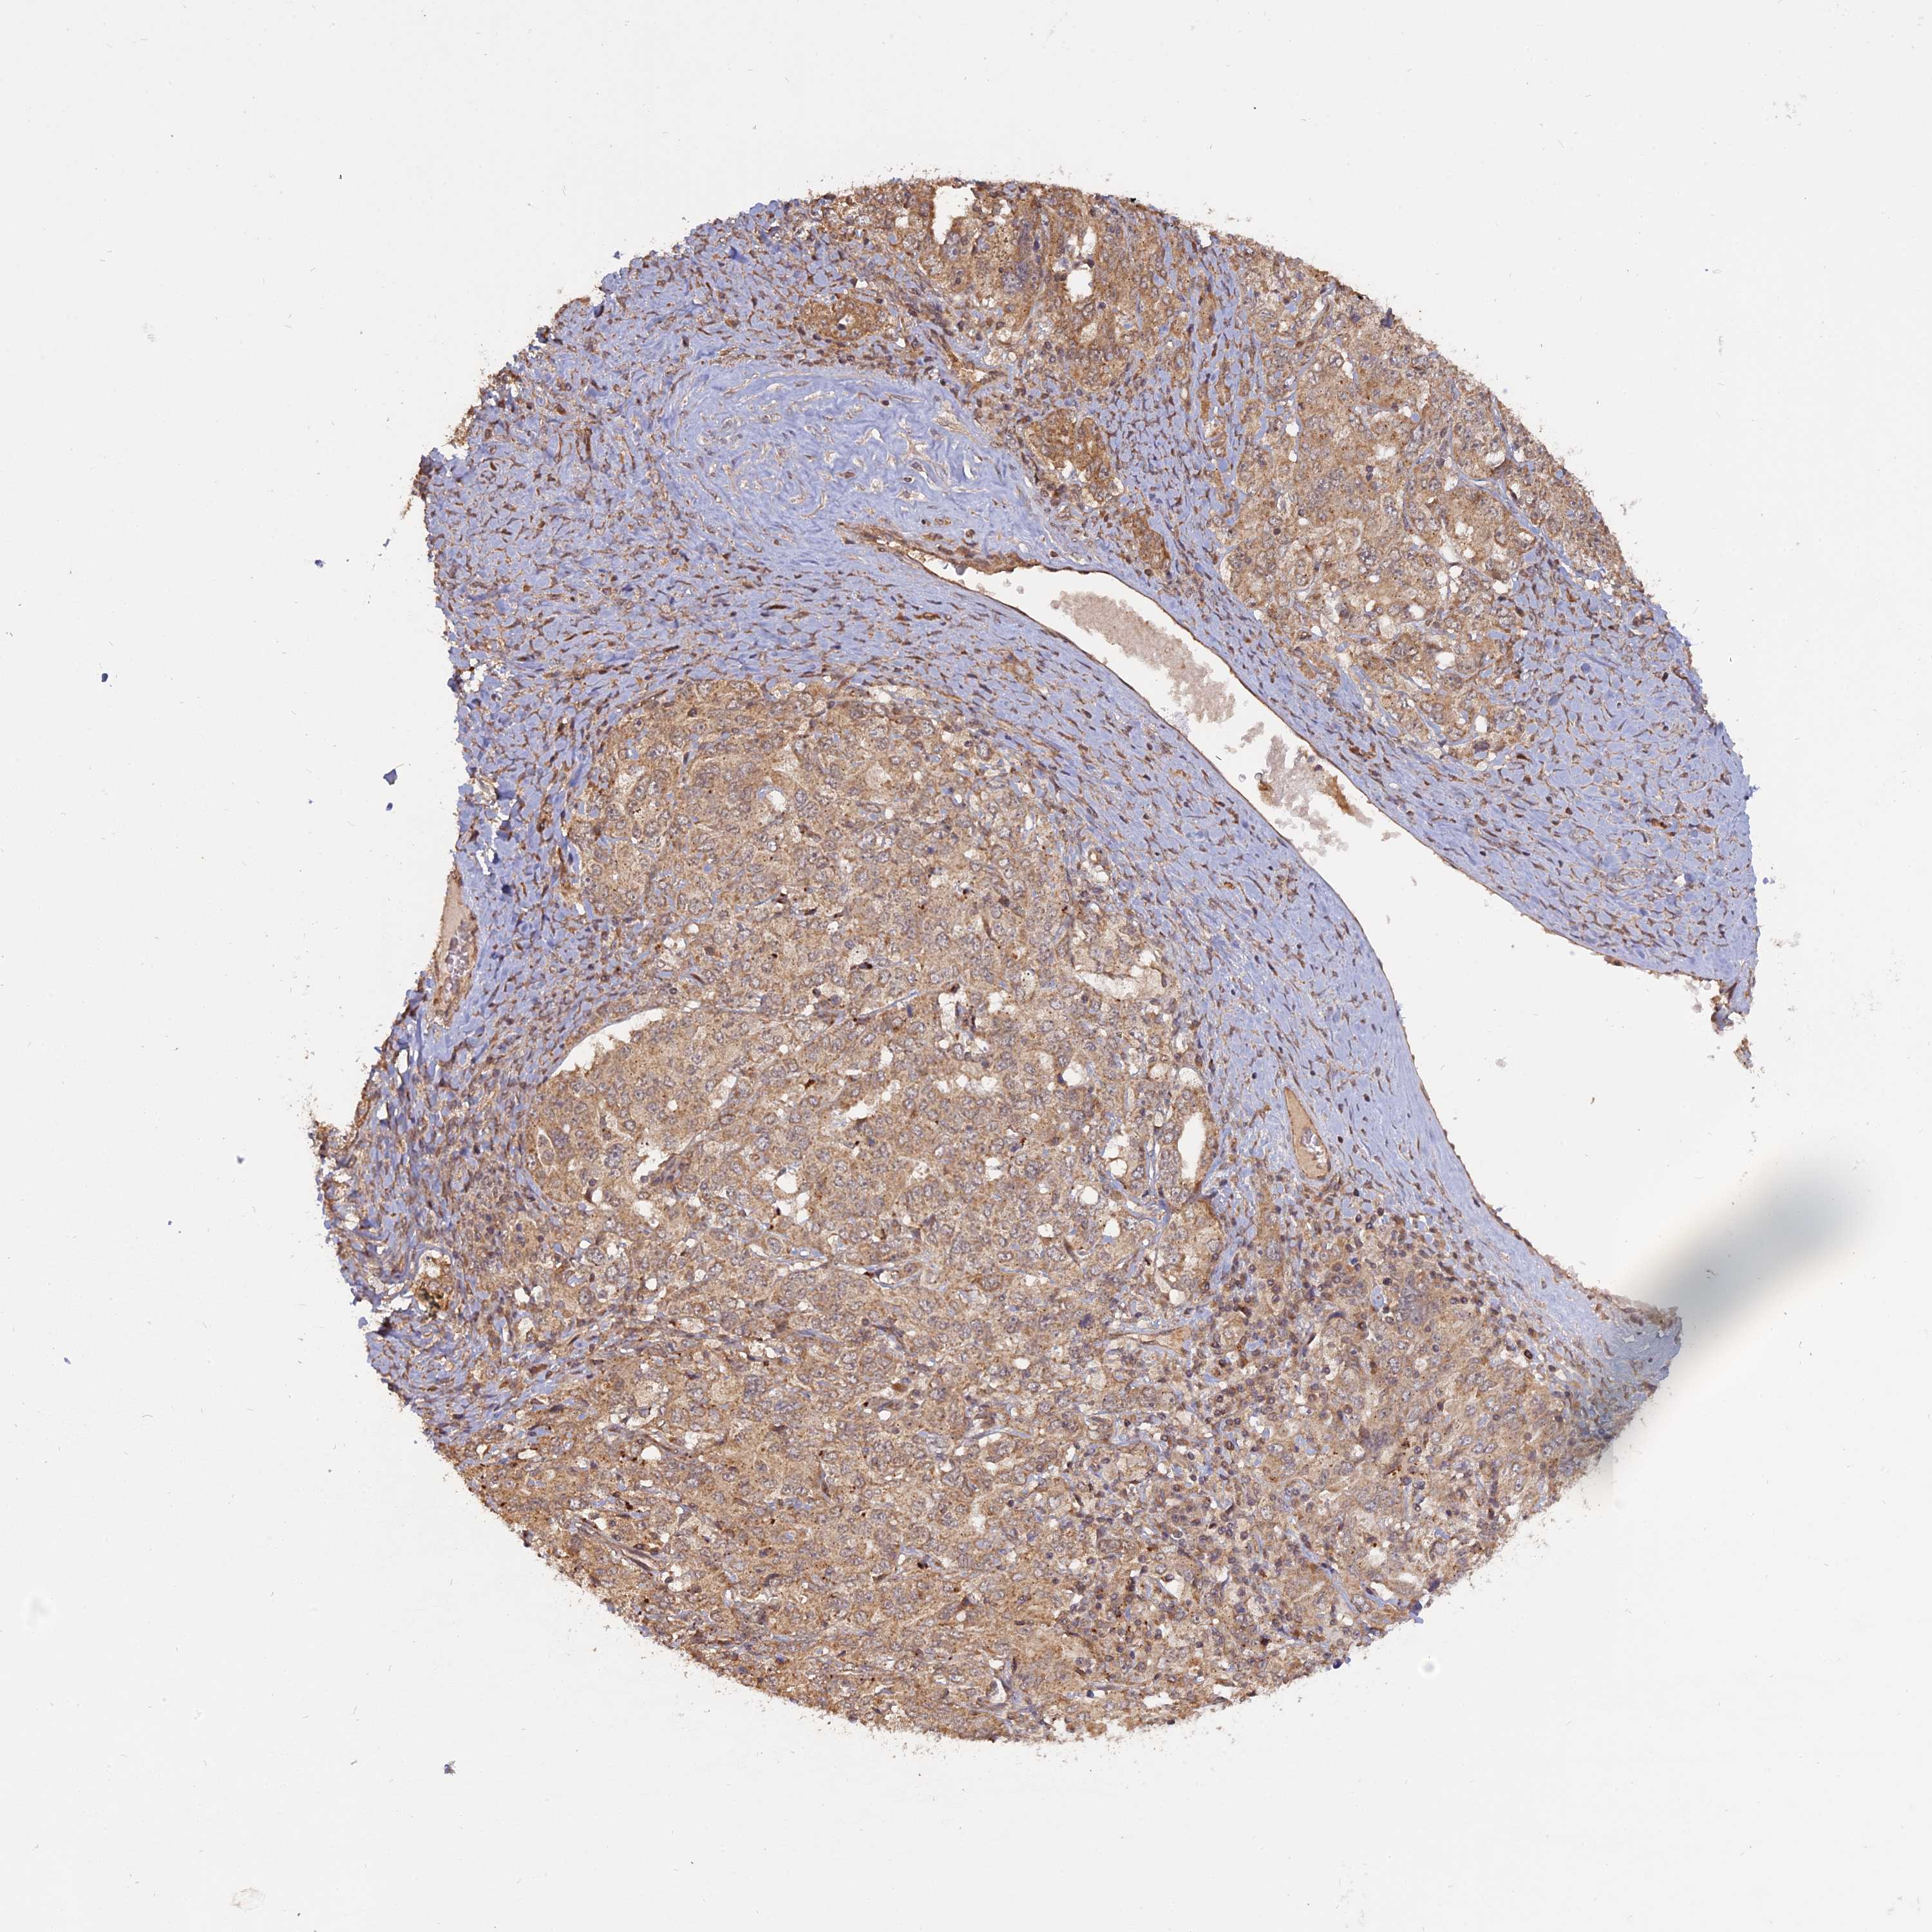

OVARIAN CANCER - Protein expressioni

A mouse-over function shows sample information and annotation data. Click on an image to view it in a full screen mode. Samples can be filtered based on level of antibody staining by selecting one or several of the following categories: high, medium, low and not detected. The assay and annotation is described here.

Note that samples used for immunohistochemistry by the Human Protein Atlas do not correspond to samples in the TCGA dataset.

Antibody stainingi

Antibody staining in the annotated cell types in the current human tissue is reported as not detected, low, medium, or high, based on conventional immunohistochemistry profiling in selected tissues. This score is based on the combination of the staining intensity and fraction of stained cells.

Each image is clickable and will lead to virtual microscopy that enables deeper exploration of all samples and also displays staining intensity scores, fraction scores and subcellular localization as well as patient and tissue information for each sample.

Antibody HPA042703

Staining

High

Medium

Low

Not detected

Intensity

Strong

Moderate

Weak

Negative

Quantity

>75%

75%-25%

<25%

None

Location

Nuclear

Cytoplasmic/membranous

Cytoplasmic/membranous,nuclear

Cystadenocarcinoma, serous, NOS

Carcinoma, endometroid

Cystadenocarcinoma, mucinous, NOS

Carcinoma, NOS